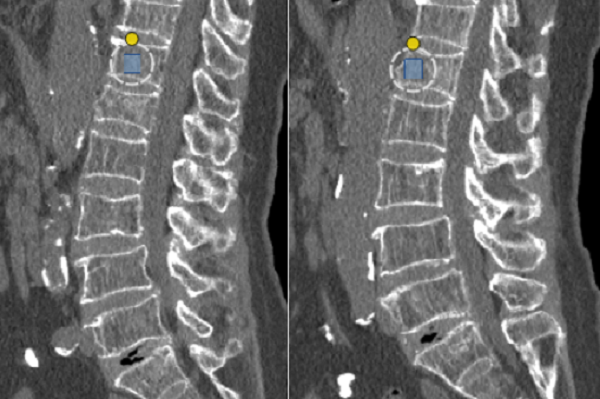

案例一: 一位奶奶扭伤腰后疼痛,做了腰椎CT和骨密度检查。结果显示腰部一节骨头有轻微裂缝,同时骨密度测量值很低,明确诊断为“严重骨质疏松”。这解释了为什么轻轻一扭就会疼痛,也提醒需要及时治疗,预防更严重的骨折。